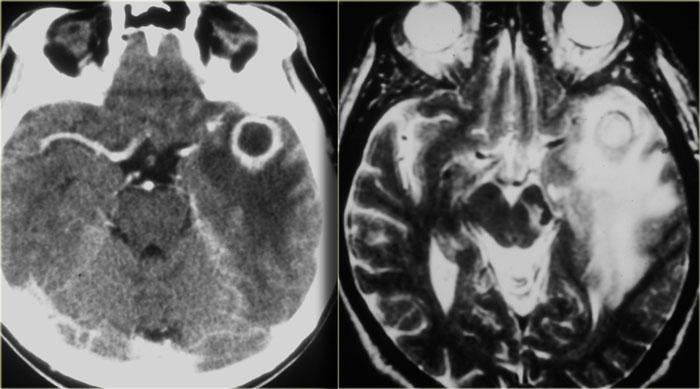

Áp xe não (2)

Hình ảnh bên trái của một bệnh nhân khác, người gần đây đã được điều trị viêm xoang và hiện nhập viện vì cơn động kinh.

CT cho thấy bất thường ở thùy thái dương trái với hình ảnh ngấm thuốc dạng vòng nhẫn dày, bờ không đều, kèm theo phù não do mạch máu lan rộng.

Đây cũng là một áp xe não, nhiều khả năng do vi khuẩn trào ngược vào các tĩnh mạch sọ và đám rối tĩnh mạch quanh xoang hang.